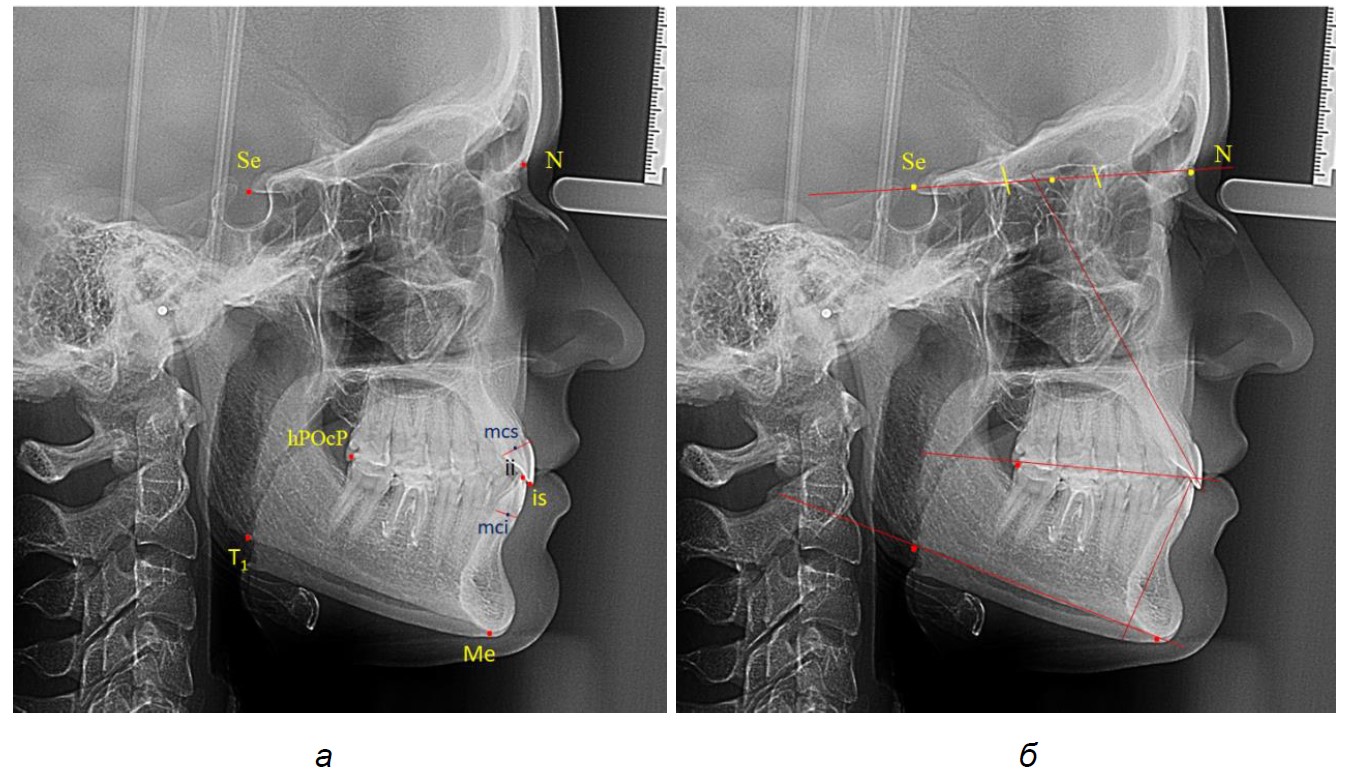

Исследование проводилось в два этапа. На первом этапе анализировали все рентегнограммы. При этом использовали общепринятые ориентиры, в частности: точки: Se; N; Me; T1; дистальную окклюзионную точку hPOcP (контактная точка окклюзии дистальной поверхности второго нижнего моляра), перхнерезцовую точку is (incisive superior – режущий край верхнего резца); нижнерезцовую точку ii (incisive inferior – режущий край нижнего резца).

Указанные точки соединяли линиями, которые служили для измерения угловых параметров (рис. 1).

Рис. 1. Расположение точек (а) и линий (б) для исследования резцов на боковой телерентгенограмме

Межрезцовый угол измеряли между условными срединными вертикалями резцов верхней и нижней челюсти. Окклюзионная линия разделяла межрезцовый угол наверхнюю и нижнюю части. Измеряли угол наклона верхнего резца к линии N-Se и угол наклона нижнего резца к мандибулярной линии. С учетом того, что межрезцовый угол весьма вариабелен, среднестатистические показатели верхнерезцового и нижнечелюстного угла были распределены по 3 типам, в частности, мезотрузионный, протрузионный и ретрузионный. Таким образом, были выделены 9 групп, для которых были рассчитаны угловые показатели.